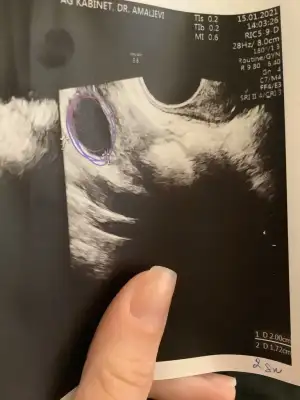

Sağolun aynen pazartesi günü randevum var en azından bir sebebim var Allah'ın izniyle çok da yüksek değilmiş hayırlısı olsunTsh gebelige engel diye biliyorum gebelik olussa dahi bebeğin sinir sistemine etkisi olabilirmis yazmistilar geçen bnce dr a gorunun içiniz rahat eder